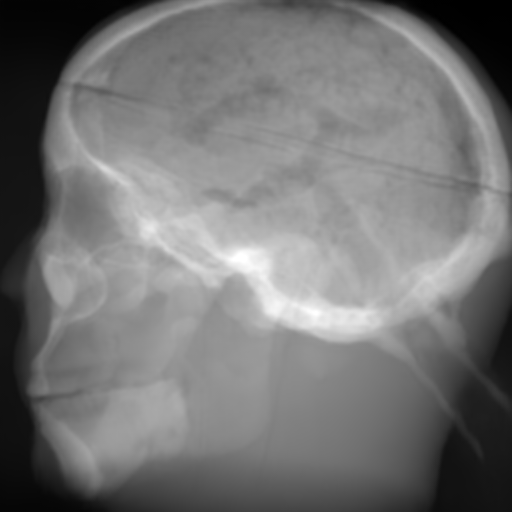

(a) Input: MR proj.

Refer to caption

(b) Output: U-net p-loss.

(c) Output: ResNet p-loss.

(d) Output: CRN p-loss.

(e) Reference: X-ray proj.

Figure 2: Results of the projection synthesis. Top row: Results generated with the perceptual-loss function. Bottom row: Results generated with the 1subscript1\ell_{1}-loss function.

The quantitative and qualitative results of the proposed experiments are presented in Table I and Figure 2. By examining these it can be observed that the differences in the calculated MSE of all network architectures and incorporated loss functions are only small. The best results in terms of pixel-wise deviation could be achieved with the ResNet architecture combined with the 1subscript1\ell_{1}-loss function. This network achieves a deviation from the reference of only 0.058, i.e., 2.4 percent. Also the results of the U-net and CRN networks are still good with deviations of 2.6 and 2.9 percent. Similarly small variation can be observed in the structured similarity measure. The ResNet and CRN exhibit approximately equal quality with SSIM measures of 0.938 and 0.920 for the 1subscript1\ell_{1}-loss and 0.924 and 0.931 for the perceptual-loss, respectively. The results generated with the U-net are slightly worse. The highest peak signal-to-noise ratio is achieved by the ResNet (1subscript1\ell_{1}-loss), followed by the U-net (1subscript1\ell_{1}-loss) and CRN (p-loss). It is noteworthy that the ResNet and U-net both achieve the highest results in all error metrics using the 1subscript1\ell_{1}-loss while the opposite is the case for the CRN which works best with the perceptual-loss function.

Overall, the perceptual-loss achieves competitive and in some cases even better results than the 1subscript1\ell_{1}-loss when comparing the pixel-wise error metrics. For example, the cascaded refinement network’s MSE is 0.013 smaller for the perceptual- than for the 1subscript1\ell_{1}-loss. This might be suspicious at first sight, considering that the 1subscript1\ell_{1}-loss purely optimizes for this pixel-wise error in the training process while the perceptual-loss compares the raw feature activations of the evaluation network. Contrarily, this behavior cannot be observed for the U-net and ResNet. The results produced with the 1subscript1\ell_{1}-loss achieve higher values for all error measures for these networks. An explanation for this obervation is that the intensity values of the input image still cause an impact on the respective layers output in the evaluation network when computing the perceptual-loss. Consequently, these differences also transition to the computed loss value for all feature layers. Even though the perceptual-loss incorporates the raw intensity values, it is not guaranteed that the scaling of these is conserved in this process. By this, the relative changes can be similar, whereas the absolute range of values changes and, correspondingly, also the pixel-wise error metrics.

Another observation is that the perceptual-loss is able to conserve high-frequency details in the image. The fine line in the projection images that forms a circle around the cranium is visible in the input (Figures 2a & 2f), as well as in the label images (Figures 2e & 2j), and also in the images generated with the perceptual-loss function (Figures 2b2c, and 2d). In contrast, all generators ”loose” this line when the 11\ell 1-loss is applied (Figures 2g2h, and 2i). This effect is also qualitatively observable in other parts of the images. Despite achieving equal or better results regarding the error metrics, the generally less sharp look of the results generated with the 11\ell 1-loss function is apparent. This behavior is in accordance with previous observations that concluded that an perceptual-loss leads to sharper images than a comparable 11\ell 1-loss [19]. Considering the common applications of X-ray Fluoroscopy, e.g., interventional guidance for stents and similar devices, high spatial resolution is a key requirement. Utilizing a loss function that is able to preserve high-frequency details in the images is desirable to this end. The perceptual-loss appears to be suited for this task as presented in our evaluation.